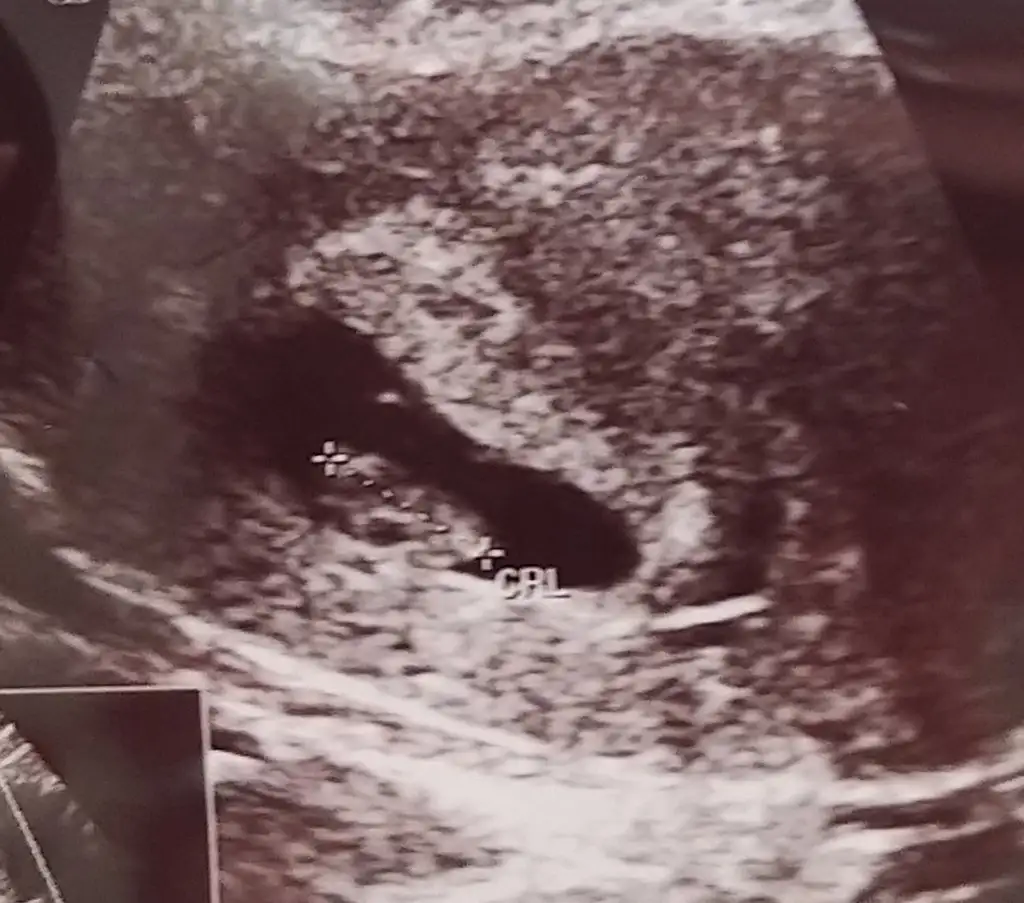

Kızlar merhaba dün yazmıştım düşük tehlikesi için bugün gittim doktora kese büyümüş şuan 17mm içinde çok minik bebeği gördüm dedi doktor etrafında kanama var dedi progestan kullanıyorum onun için. Yalnız beta hcg bakalım dedi 27700 çıktı doktor bu değerde kalp atışı olması gerekirdi dedi iki gün sonra tekrar bakıcaz değer artıyormu diye sizin beta kaçken duyulmuştu kalp atışı şuan 5+4 haftalık ama ultrasonda 6+1 görünüyor

Evet haklısın aslında ultrason çekilirken videoya aldık da dr oynattikca kese değişiyordu. Ramziye göre sence kız mi benim? Biraz geride kaldi görüntü gerci